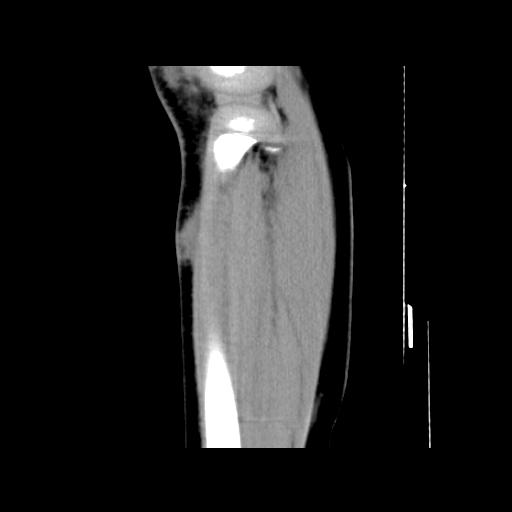

标题: PED0931:男,5岁,发现双小腿软组织肿块1年,质地中等,无 [打印本页]

标题: PED0931:男,5岁,发现双小腿软组织肿块1年,质地中等,无